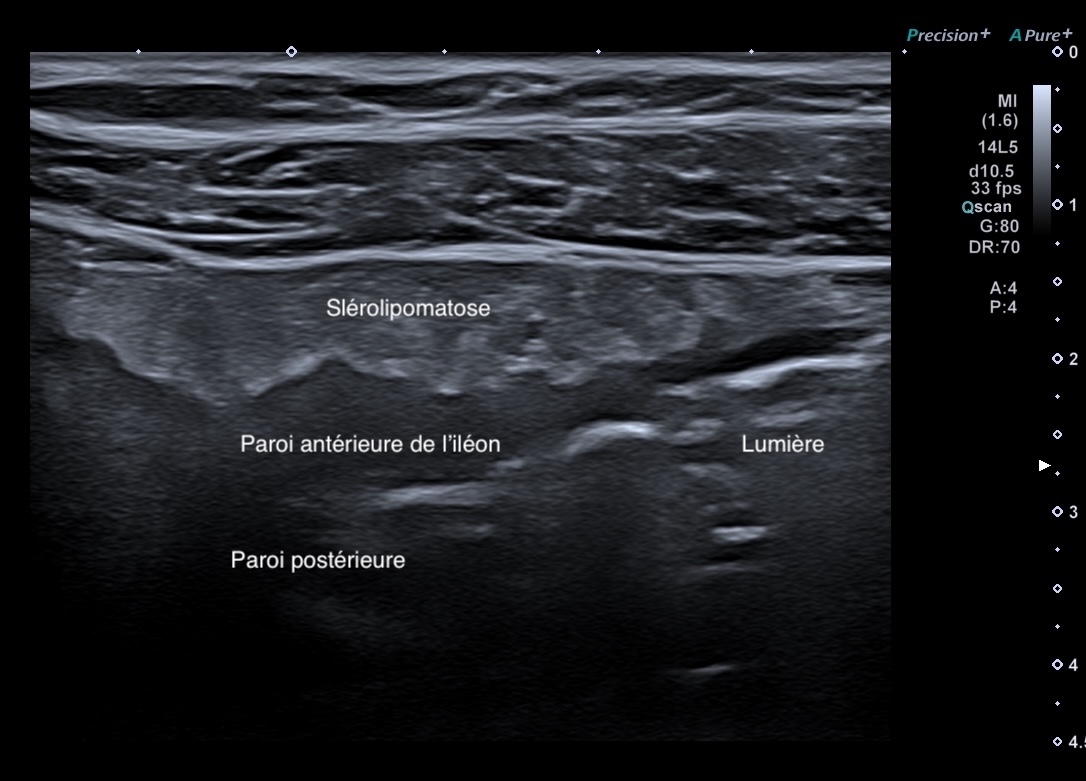

C'est la forme chronique de l'inflammation de la graisse, l'inflammation devient scléreuse, figée arrondie, plus hypoéchogène

- attraction de la séreuse en profondeur qui prend un aspect spiculé

- plus hypoéchogène

- Déformant la paroi localement

Sclérolipomatose antérieure iléon, graisse hypo échogène paroi Limberg 1 au maximum